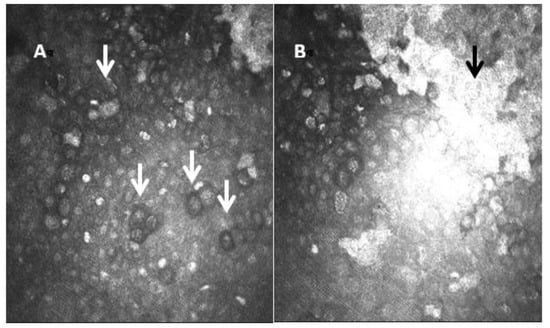

One of the most important applications of IVCM is to help in the diagnosis of a potentially severe ocular surface disease, such as Acanthamoeba keratitis (AK). AK is an infectious keratitis that represents a clinical challenge. Delays in diagnosis due to the challenging, masquerading presentation of AK are evident, and thus AK is one of the most aggressive corneal infections. The Acanthamoeba resistance to some drugs requires novel treatment approaches. The diagnosis of AK begins with the clinical suspicion [34]. IVCM can be effectively used to improve the diagnostic accuracy. The Acanthamoeba organisms have a characteristic morphology, and the use of IVCM plays an important role in the early diagnosis. The sensitivity of IVCM to help in AK diagnosis is about to 59.0 to 100%, depending mainly on the examiner expertise [35,36,37]. The Acanthamoeba organisms have specific morphological features that support the diagnosis. The most common features are: hyperreflective bodies with a round shape with double wall which can be found isolated or in clusters, and a target bright cyst with a dark center or ring-shaped signs [35,36]. The IVCM showing deeper diffusion and increased cyst density [38,39] are associated with a worse prognosis. In addition to its role in the diagnosis of AK, IVCM can also be used to assess for treatment response and examine for residual disease [40]. Figure 6 shows IVCM images of AK.

Figure 6.

Laser confocal microscopic images of Acanthamoeba cysts. In image (A), the cysts show a highly reflective nucleus surrounded by a low-refractile ring wall (white arrows). The central structure is regular and round with uniform reflection. In image (B) we also see a hyperreflective scar (black arrow).